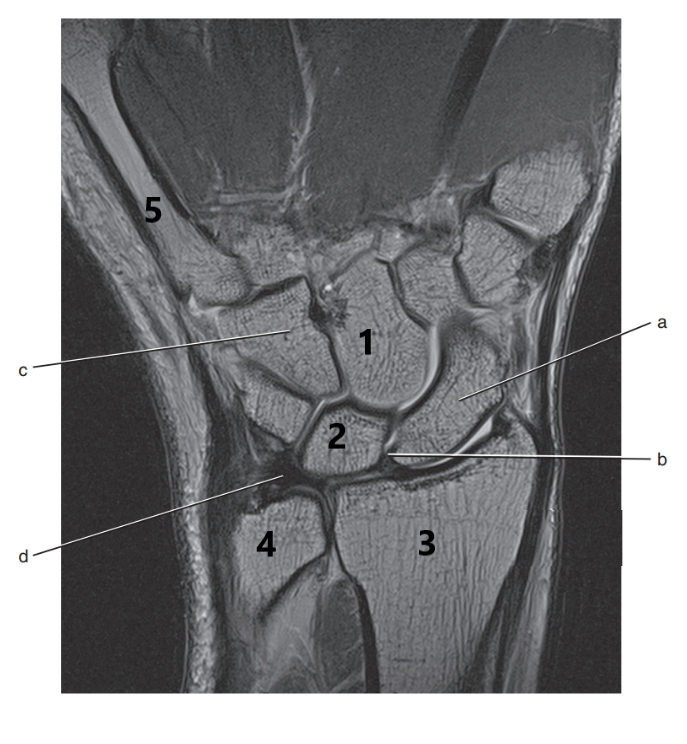

What anatomy is # 2 ?

Scapula

What anatomy is # 1 ?

Humeral head

What is # 2 ?

Lunate

What is # 1 ?

humerus

Ulna